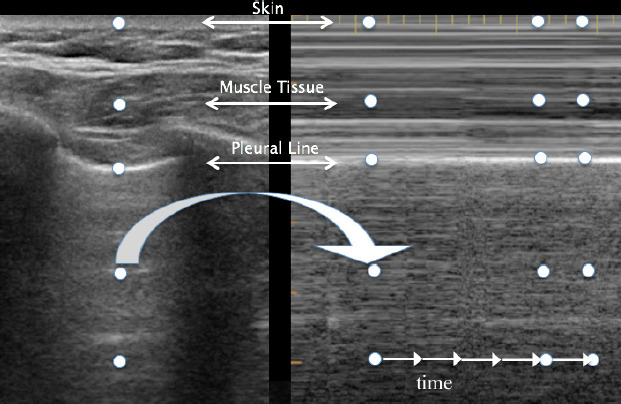

Abstract Image